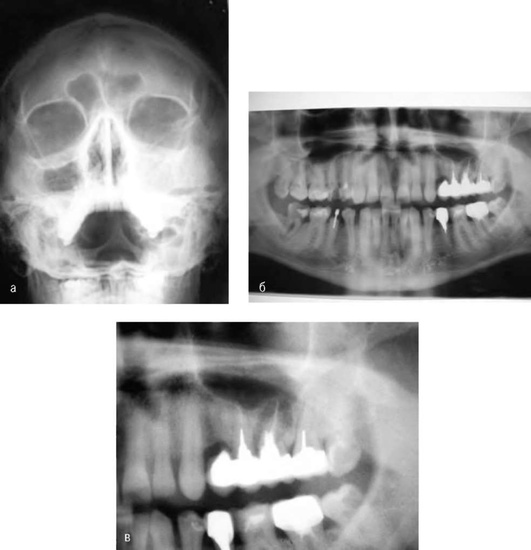

Клиническая характеристика периодонтита слагается из ряда симптомов и параклинических методов диагностики. Диагноз в целом ряде случаев может быть установлен лишь на основании всего комплекса данных, полученных при сборе анамнеза и применении различных исследований. Обследование пациента включает: жалобы, историю развития настоящего заболевания, статус здоровья, перенесенные и сопутствующие заболевания, клинические исследования (осмотр, пальпация, перкуссия); электроодонтодиагностику, рентгенологические исследования (внутриротовые и внеротовые рентгенограммы в различных проекциях, ортопантомограммы, фистулографию, радиовизиографию, компьютерную томографию и магнитно-резонансную томографию, специальные функциональные методы, лабораторные исследования (цитологические, патоморфологические, клинический анализ крови и иммунограмма, биохимические исследования, анализ мочи и др.).

Рентгенологически при остром периодонтите обычно не наблюдают видимых изменений в периодонте. При этом компактная пластинка альвеолы бывает невредимой и гладко очерченной. Ширина и очертания периодонтального пространства не изменены, так как накопившийся в нем серозно-гнойный или гнойный экссудат не обладает рентгеноконтрастностью. При выраженной остеолитической интенсивности процесса можно иногда наблюдать расширение периодонтальной щели и слабые деструктивные изменения. У некоторых больных может определяться потеря чёткости рисунка губчатого вещества костной ткани - диффузия (рис. 13-6).

image

Рис. 13-6. Острый апикальный периодонтит. Схема диффузии: 1 - стадия интоксикации; 2 - стадия экссудации (апикальный абсцесс); 3 - прогрессирование воспалительного процесса при сохранении кортикальной пластинки альвеолы (поднадкостничный абсцесс); 4 - с разрушением кортикальной пластинки костной альвеолы (поддесневой абсцесс)